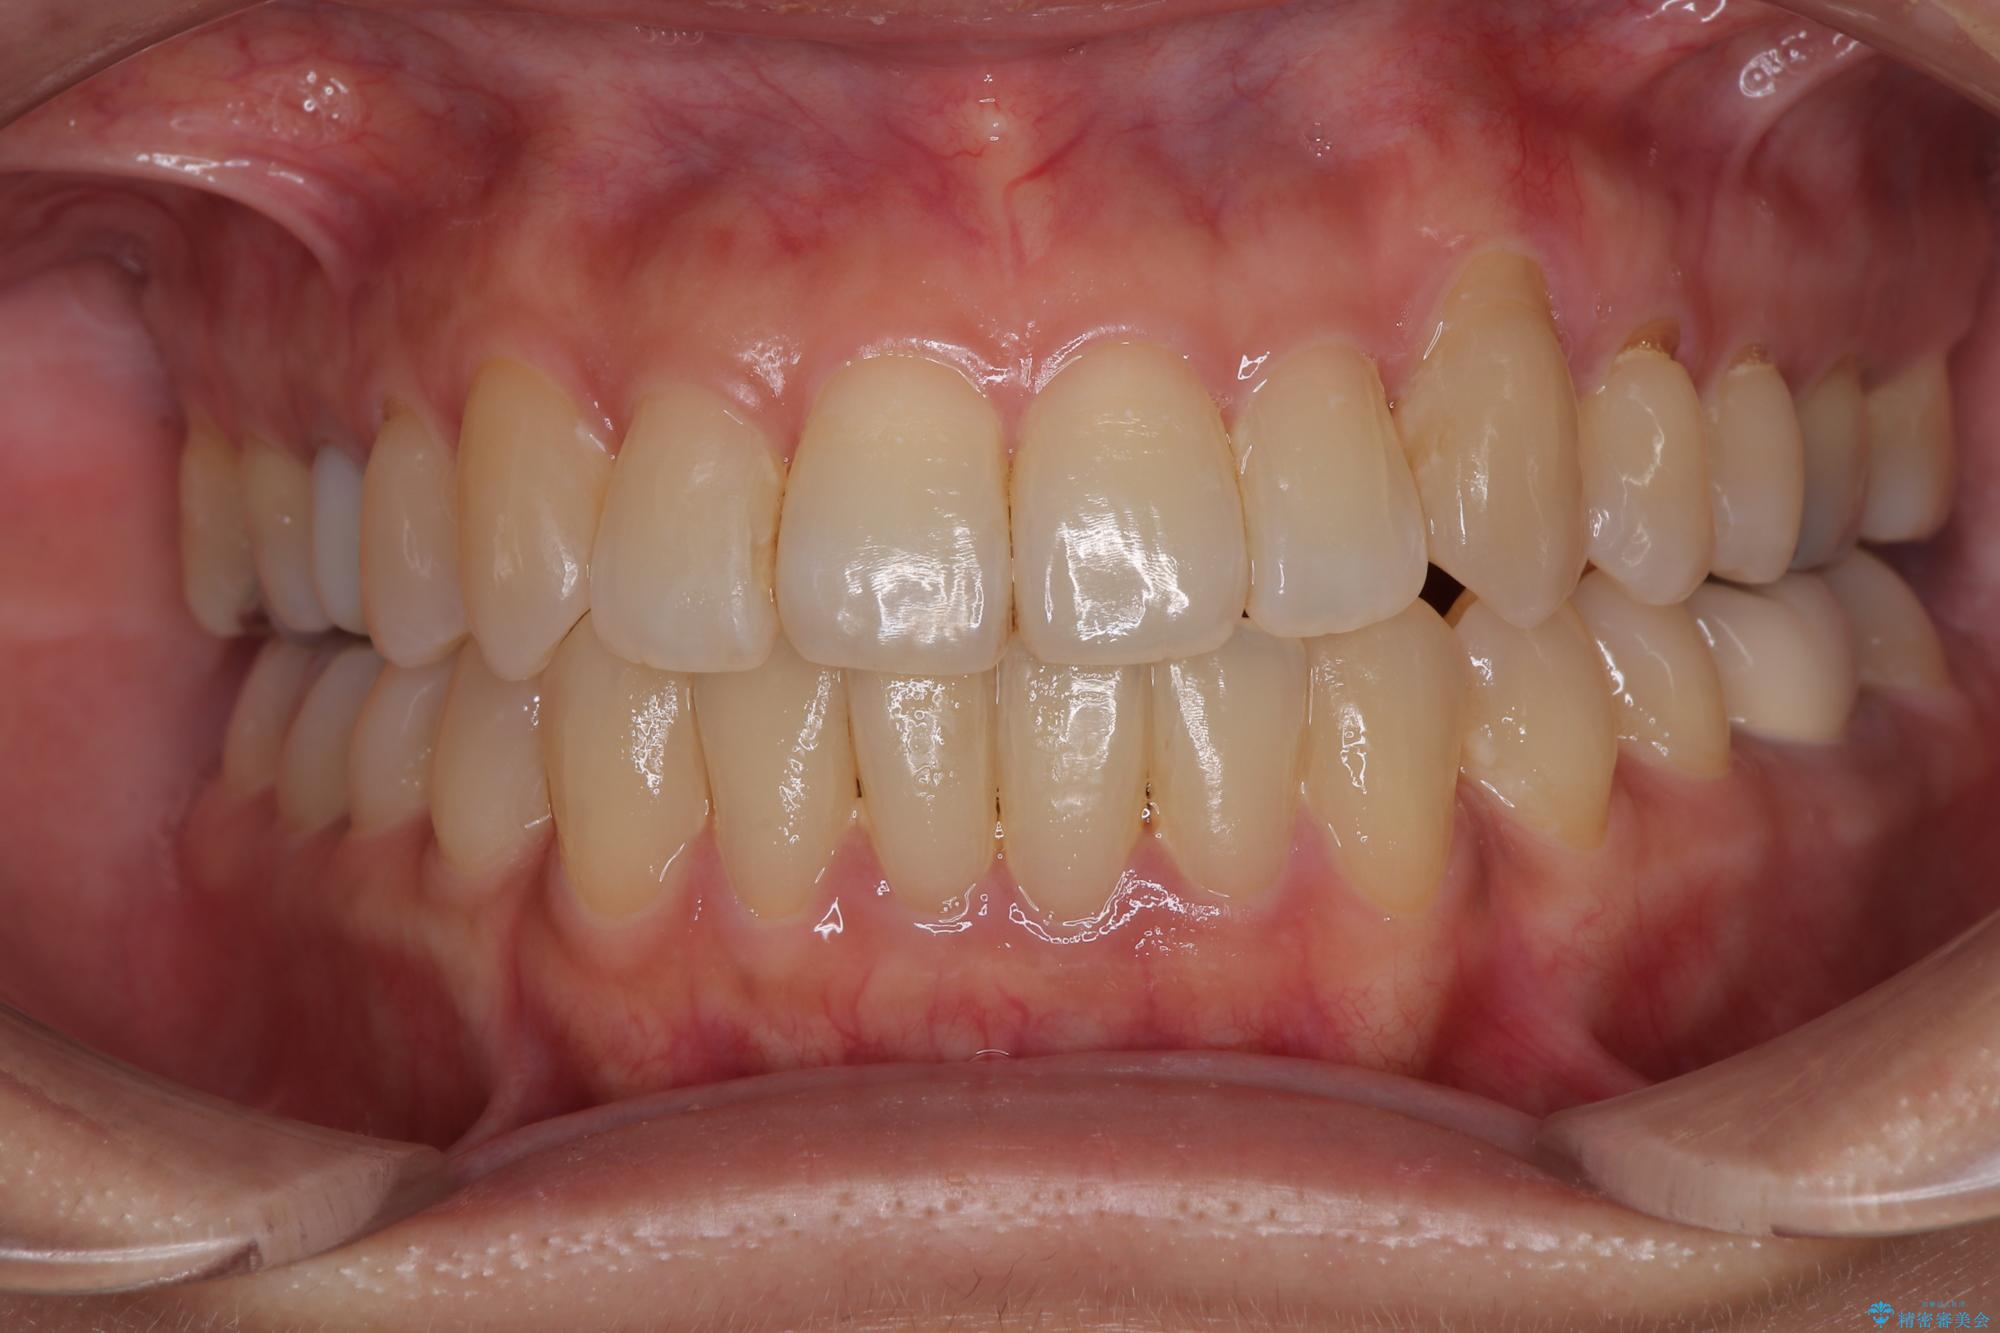

受け口と八重歯を改善 インビザライン矯正治療

- 前歯のデコボコや八重歯を治したいとのことで来院された患者様です。

受け口傾向の骨格であり、前歯はクロスバイトまたは切端咬合となっており、下顎を中心に歯列全体の後方移動を行い、IPR(歯と歯の間を削る)によってデコボコが解消するように設計し、インビザラインにより治療を行うこととしました。

受け口傾向のインビザライン矯正は比較的治療を行いやすいため、きれいに仕上げることができました。舌の突出癖が顕著であったため、改善のためのトレーニングをしっかりと行っていただきました。